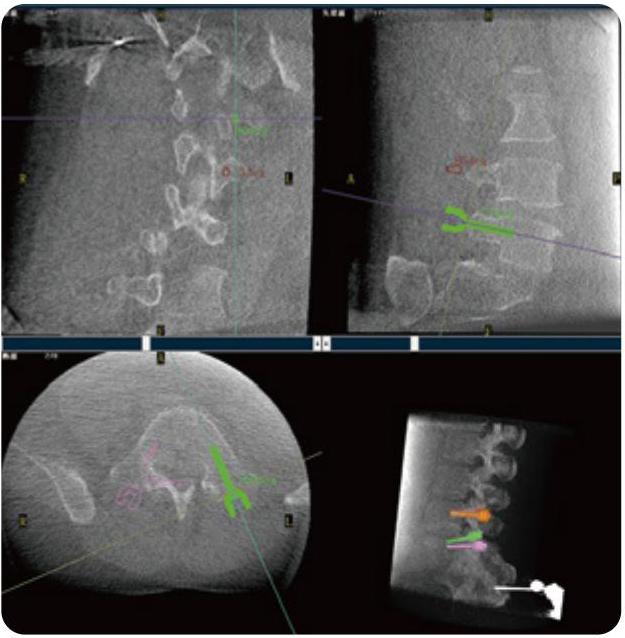

PL300B可應用于多節段脊柱外科手術(shù),輔助醫生定位病灶部位,為脊柱外科手術(shù)(經(jīng)皮椎體成形術(shù)、椎弓根螺釘內固定術(shù)等術(shù)式)提供術(shù)前手術(shù)流程規劃、入釘位置、角度可視化引導,模擬仿真入釘輔助。

PL300B搭配普愛(ài)醫療自主研發(fā)生產(chǎn)的平板3D C形臂,借助一體化自適應配準( 軌跡配準)技術(shù),通過(guò)追蹤C形臂三維采集軌跡,自動(dòng)完成圖像坐標建立和系統坐標配準。配準精度更高,操作步驟少,系統運作效率高。